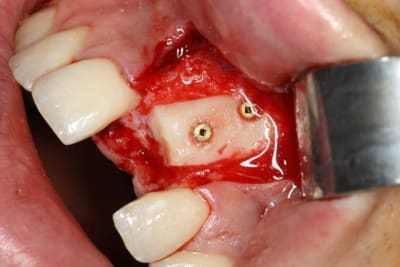

les quelques photos (déjà publiées) greffes avec flap à droite et chaussette flapless à gauche.

implant avec spreader (condensation) à droite et ostéotomes (Tatum et divers) à gauche.

Si ça fond, je vais regretter d'avoir piqué le patient à Tulasne, qui avait programmé du pariétal (vestibulaire et palatin).

D'autant plus que je me suis fait gonfler les chevilles car c'était semble t il une première mondiale (greffon préparé d'après modèle 3D avant le traitement de la tête de fémur et sa stérilisation)

Img 7141r ylzwwe - Eugenol

Img 7150r tgalxt - Eugenol

Img 7165r raakzy - Eugenol

Img 7155r mvdccj - Eugenol

Img 7162r fldzar - Eugenol